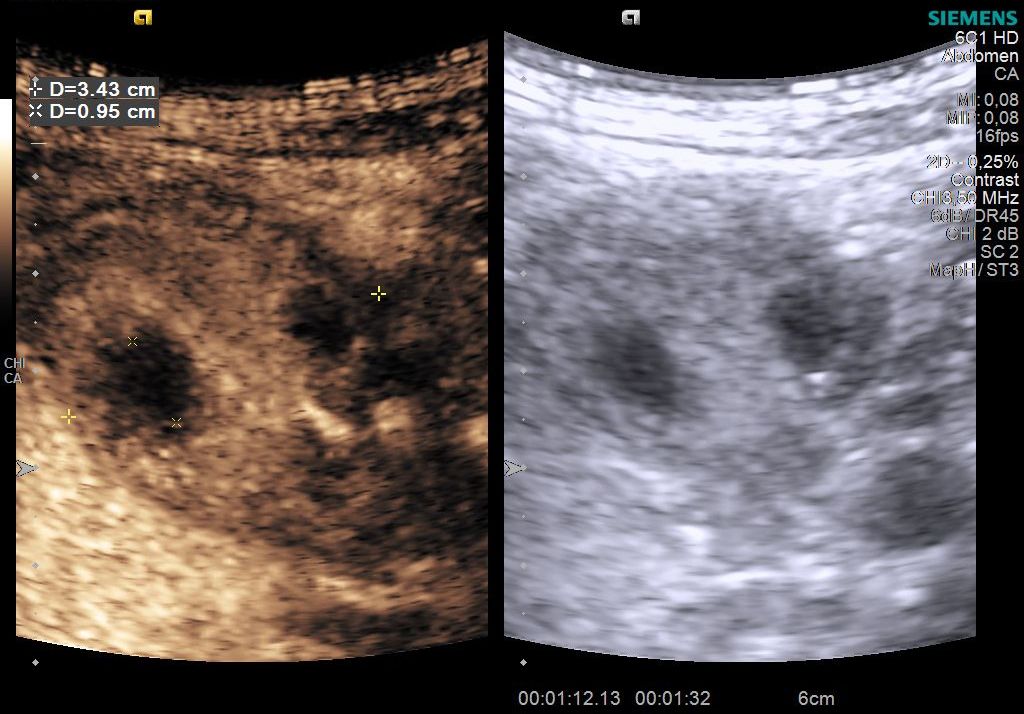

Case courtesy of Prof Adrian Saftoiu

Student Image Challenge 80